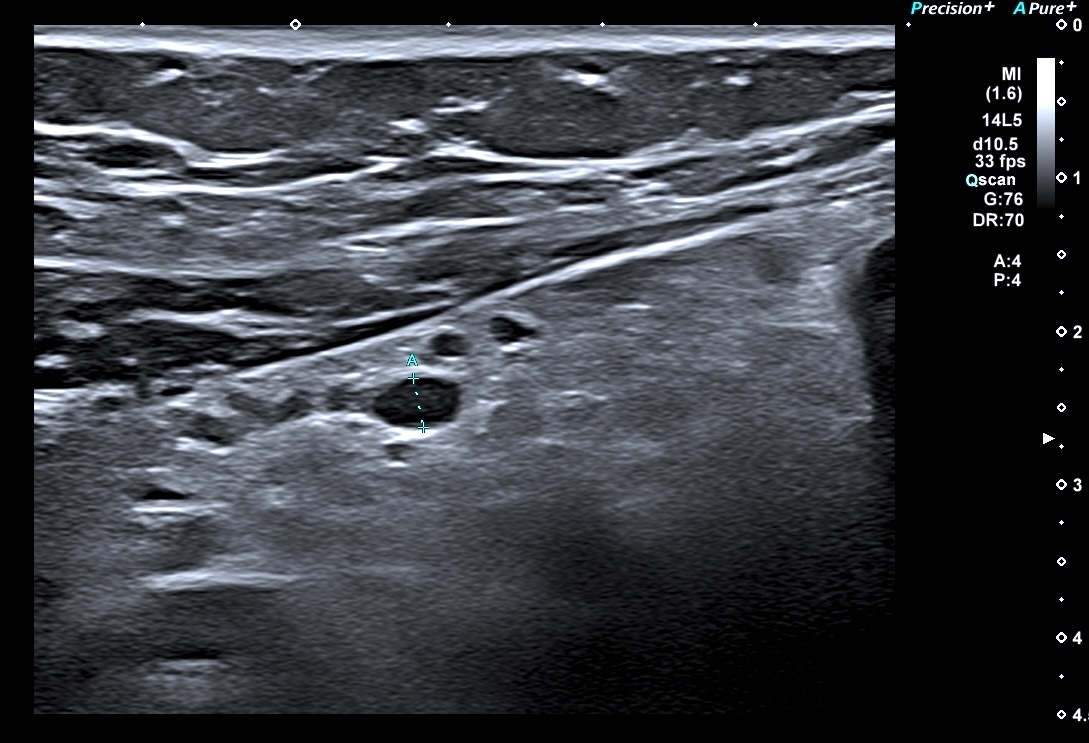

Exemple de paroi de 5 mm avec début de la disparition de la structure en couches (le contraste entre la muqueuse et la sous muqueuse est moins visible)

L'épaississement est encore plus important (8 mm), la surfacede la lumière devient irrégulière

Sur un sigmoide dans une forme récente, la muqueuse est plus épaisse, on a parfois un faux aspect d'irrégularité, mais la structure en couches est conservée